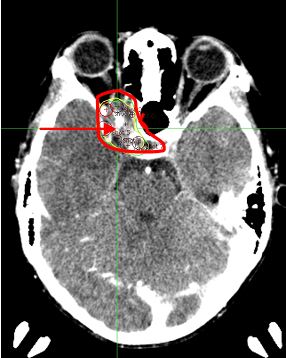

2. Bệnh nhi Nguyễn Viết T., nam 11 tuổi.  Vào viện vì đau đầu, mờ mắt phải, sụp mi mắt phải. Cách ngày vào viện 4 tháng bệnh nhân đau đầu và mờ mắt ngày càng tăng dần, sau đó sụp mi mắt phải. Tại bệnh viện Bạch Mai bệnh nhi (BN) được chẩn đoán khối u màng não vùng nền sọ và hốc mắt phải đường kính 31x55x23mm, xâm lấn xoang bướm và bao quanh động mạch cảnh trong phải. BN được chỉ định điều trị xạ phẫu gamma knife liều 14Gy. Sau điều trị khoảng 1 tháng thị lực mắt phải của bệnh nhi được cải thiện nhiều (trước điều trị thị lực mắt phải 1/10; sau điều trị 7/10) hết đau đầu và sụp mi. Trên phim chụp cắt lớp vi tính sọ não: hình ảnh khối u đã thu nhỏ kích thước hơn trước

Hình  ảnh u  trước  điều  trị:  khối  u  màng não vùng nền sọ và hốc mắt  phải  đường kính 31x55x23mm, xâm lấn xoang  bướm và bao quanh động mạch cảnh trong phải

Sau điều trị 1 tháng: khối u thu nhỏ kích  thước hơn trước, đường kính 20x15mm